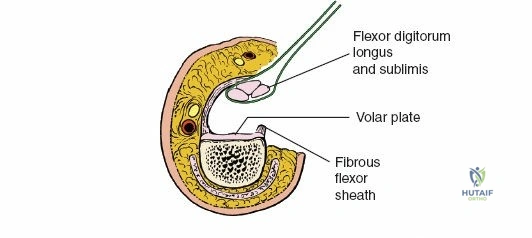

A thorough understanding of the intricate anatomy and biomechanics of the flexor tendon system is non-negotiable for any surgeon employing a volar approach. The digital flexor system comprises the Flexor Digitorum Superficialis (FDS) and Flexor Digitorum Profundus (FDP) tendons. The FDP tendon originates from the ulna and interosseous membrane, inserting onto the volar base of the distal phalanx, primarily responsible for DIP joint flexion. The FDS tendon originates from the medial epicondyle, ulna, and radius, typically bifurcating around the FDP in the region of the proximal phalanx (Camper's chiasm) before inserting onto the middle phalanx, primarily flexing the PIP joint.

Within the fibro-osseous tunnel, these tendons are enveloped by a synovial sheath that facilitates smooth gliding and nutrition. The integrity of the pulley system, composed of annular (A) and cruciate (C) ligaments, is critical for preventing tendon bowstringing and maintaining efficient mechanical advantage. Typically, five annular pulleys (A1-A5) and three cruciate pulleys (C1-C3) are described in each finger. The A1 pulley is at the metacarpophalangeal (MCP) joint level, A2 at the proximal phalanx, A3 at the proximal interphalangeal (PIP) joint, A4 at the middle phalanx, and A5 at the distal interphalangeal (DIP) joint. The A2 and A4 pulleys are considered the most critical for preventing significant bowstringing.

Once the subcutaneous tissue and neurovascular bundles are retracted, the fibrous flexor sheath is visible. This appears as a glistening white, tough structure enveloping the flexor tendons.

The sheath is incised longitudinally. The specific pulleys that need to be released depend on the pathology and zone of injury.

- For flexor tendon repair, typically the A2 and A4 pulleys must be preserved to prevent bowstringing, which significantly impairs mechanical efficiency.

- The A1, A3, and A5 pulleys, and the cruciate pulleys (C1, C2, C3), can be incised longitudinally or partially vented to expose the tendons and allow for repair.

- When accessing Zone II (no-man's land), the incision usually involves opening the A1, A3, and C1/C2/C3 pulleys, carefully preserving the A2 and A4 pulleys.

- Pulley Management: The consensus emphasizes the critical importance of preserving the A2 and A4 pulleys in the digits to prevent functional bowstringing. Division of A1, A3, and A5, and the cruciate pulleys, is generally well-tolerated and often necessary for adequate exposure and debridement. In situations where A2 or A4 must be sacrificed, elective pulley reconstruction at a later stage may be considered using tendon grafts (e.g., palmaris longus) or fascia.